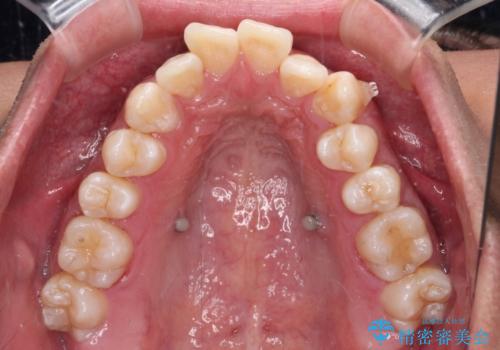

歯列としてはインビザラインでもワイヤー矯正でも対応できるものでしたが、上顎の八重歯や下顎小臼歯の捻転といったインビザラインでは時間のかかってしまう歯列不正が認められたため、補助装置やワイヤー矯正を治療当初に使用することで、インビザラインによる治療をスムーズに行えるように計画しました。

インビザラインは得意・不得意の差がはっきりとしているため、ワイヤー装置などをうまく活用することで、治療期間を短縮するとともに、より理想的な仕上がりを達成することができます。